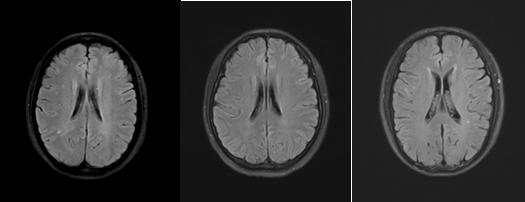

(FLAIR序列及T2WI序列显示缺血性脱髓鞘病变)

髓腔脱失的原因有很多,包括先天代谢性和后获得性。先天代谢性脱髓鞘主要指的是脑白质营养不良,以儿童青少年起病居多,这类疾病脱髓鞘在影像上多呈广泛对称性。后天性获得性脱髓鞘的病因又有很多种,包括缺血、炎症、感染、代谢、中毒、外伤等。更多见的是由高血压、糖尿病、高血脂等造成的微小血管病变引起缺血,继而导致髓鞘的脱失,也就是我们最常见的缺血性脱髓鞘,其本质是脑梗塞。这些脱髓鞘往往是个慢性的过程,一般没有临床症状,只有在做颅脑核磁检查时才被发现;病灶个头通常较小,数量上有时个别几个,有时候也可以有不少,呈点灶状或小片状分布在皮层下或者深部脑白质或者侧脑室前后角旁。看专科医生时,如果判断属于这种类型的脱髓鞘,就需要对上述相关的危险因素进行筛查、监测和管理,并完善颈部血管超声、经颅多普勒、颅内血管核磁等检查,看看大中血管的情况,如果没有比较大的斑块,没有明确的血管狭窄。就要管理危险因素(血压、血糖、血脂、吸烟过量饮酒等)并每半年到一年复查一下就行了。